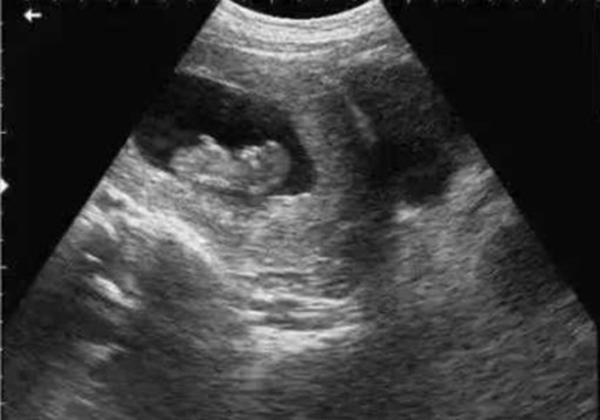

? 超聲檢查(B超/彩超):它利用超聲波的反射原理成像,就像“用聲音給身體拍照片”,沒有任何輻射。無論是孕期產(chǎn)檢(觀察胎兒發(fā)育)、腹部檢查(排查肝脾膽囊問題),還是甲狀腺、乳腺等淺表器官檢查,超聲都是首選。而且超聲檢查靈活便捷,還能實時動態(tài)觀察器官運動(比如心臟跳動、胎兒胎動),是臨床中應用最廣泛的“安全檢查”。